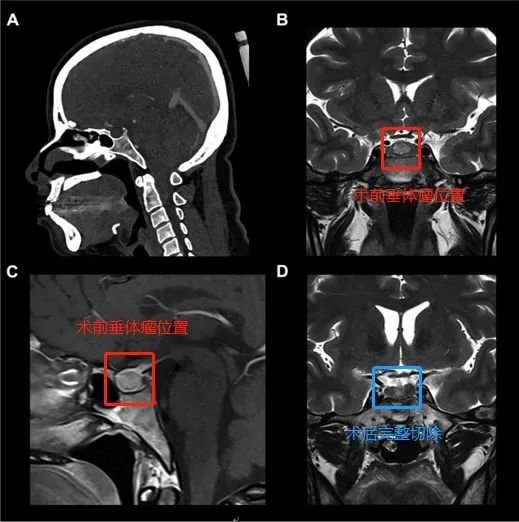

37岁女性蝶鞍中央垂体瘤